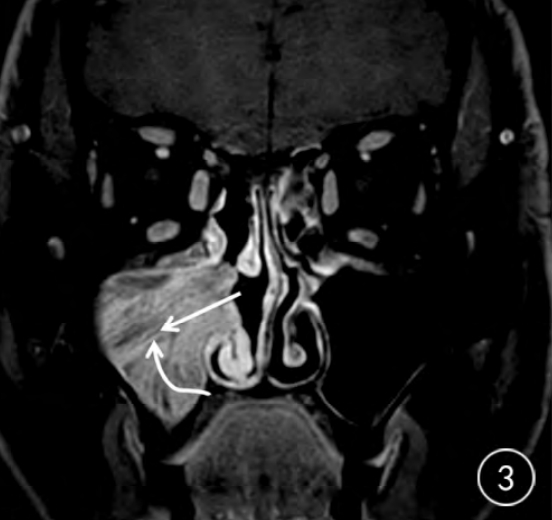

4、鼻腔检查可发现红色肿物,乳头状增生,可伴有脓涕。肉眼有时和鼻息肉难以鉴别。CT检查可见鼻腔、鼻窦软组织密度影,部分区域可见骨质压迫变薄或者骨质增生。MRI可利用信号变化来区分肿瘤包块和阻塞性分泌物,典型表现可见栅栏征或脑回征像。(下图显示手术病理标本)

1)CT和MRI是术前预测肿瘤根蒂的关键。CT显示骨质增生、气泡征等有助于肿瘤根蒂的定位。MRI可以清楚显示病变的起源部位、生长方向、大小。(下图左CT2显示右侧筛窦骨质增厚,提示根蒂部)(下图右,MRI3现实右侧上颌窦栅栏或脑回征,提示内翻性乳头状瘤。)